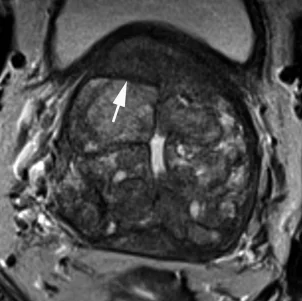

Очаг выраженного ограничения диффузии (гипо- на ADC, гипер- на DWI), менее 1.5 см

То же что и PIRADS 4, только размером более 1.5см

Вытянутой формы или не ограниченная гипоинтенсивная гомогенная зона, менее 1.5см

То же что и PIRADS 4, только размером более 1.5см или с распространением за пределы простаты